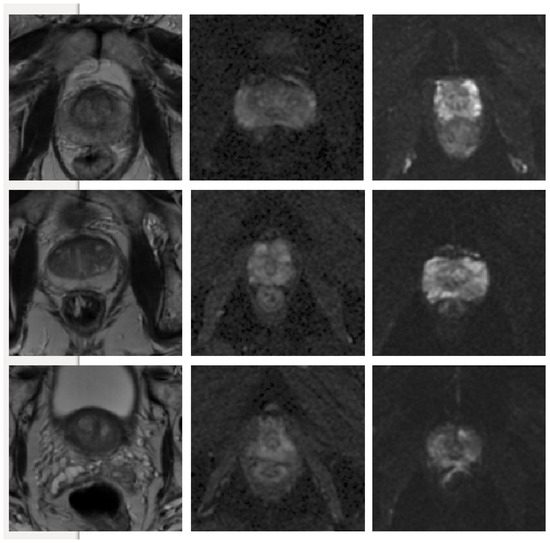

In terms of the T2W modality, similar outcome was achieved with regards to the training samples used during learning procedure for the cGAN model. The combination of raw and GNA was the best in the cGAN model; while the combination of raw and SP obtained the best output results in the cycleGAN model. To justify this by investigating the T2W modality images, we observed that the images in this modality show anatomy, especially the peri-prostatic structures, more clearly than other modalities. Figure 6 shows that ADC and DWI images have low signal around the prostate compared to the T2W modality. Superpixelizing the T2W images groups the pixels better and makes the surrounding anatomy more visible for the cycleGAN network. In the cycleGAN model there are two different domains and there is no paired input-output relation between them. The generators are penalized by the adversarial loss with the cycle consistency loss, which forces the generators to not only do the segmentation but also synthesize the original MR image from the created mask back again. As a result, the network learns a mapping between the training images and their masks and vice versa. Therefore, for the SP approach, learning is more optimised. When we compare the results of the raw plus SP images on the three modalities in the cycleGAN model, it is also consistent with this result that training using the T2W modality images obtained the best results (with DSC values of 0.748) while the DSC outcomes for DWI and ADC modalities were 0.702 and 0.710, respectively. For the DWI modality, the best results for the cGAN and cycleGAN models were achieved by using the raw plus MM images as the training set. The MM approach removes the unnecessary details from an image helping the network to focus on prostate tissue as the target part of the image during the training process. It shows consistent results with regards to the three evaluation metrics. The ROC curves and AUC values for these networks, applied to three modalities (ADC, DWI and T2W), are shown in Figure 7.

Figure 6.

Some examples of T2W, ADC and DWI MR images from our dataset, which demonstrates that DWI and ADC modalities have lower signal around the prostate compared to the T2W modality. Scaled images are shown in Figure A2 for better visualisation.

Figure A2.

Some examples of T2W, ADC and DWI MR images from our dataset, which demonstrates that DWI and ADC modalities have lower signal around the prostate compared to the T2W modality.